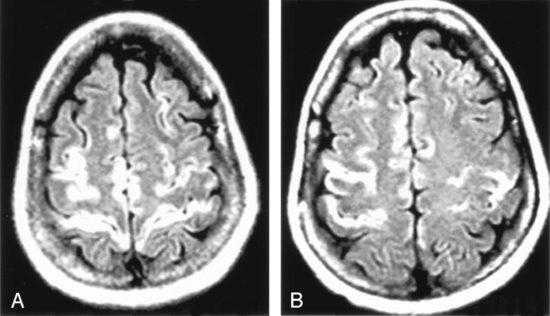

У пациентки восстановилось сознание, она стала контактна, адекватна, ориентирована, критична. Дизартрия незначительная. По остальным органам и системам без динамики. К моменту выписки клинически значимых изменений в общем и биохимическом анализах крови не отмечалось. На фоне АРВТ нагрузка ВИЧ в крови снизилась до 709 копий в 1 мл, однако уровень лимфоцитов CD4 составлял 163 в 1 мкл (19%). После курса лечения цимевеном ДНК ЦМВ в клетках крови не обнаружена. В ликворе положительная динамика в виде снижения цитоза до 1 клетки в 1 мкл, снижения уровня белка с 0,69 до 0,55 г/л, РНК ВИЧ 20 копий в 1 мл. При последующих исследованиях ликвора ДНК JC-вируса обнаружить не удавалось. На повторном снимке МРТ головного мозга отмечалась отрицательная динамика в виде увеличения зоны патологических изменений с распространением диффузного билатерального симметричного поражения средних ножек мозжечка, определения патологической зоны в правой ножке мозга.

При МРТ головного мозга (от 05.07.15) картина очаговых и диффузных изменений вещества (в лобных долях интрасубкортикально очаги повышенного МР-сигнала без признаков перифокального отека до 0,4×0,3 см, в гемисферах мозжечка — диффузные зоны повышенного МР-сигнала без признаков перифокального отека).

При МРТ картина ПМЛ типичная:

- выявляются несимметричные участки высокого сигнала на Т2-зависимых томограммах, преимущественно, в теменных и затылочных долях;

- поражение распространяются до подкорковых зон;

- масс-эффекта нет;

- контрастирование бывает редко, с быстрым увеличением и слиянием очагов.